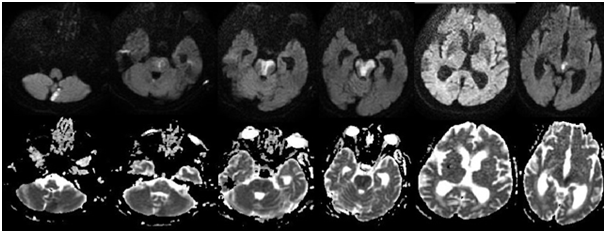

A 84-year-old woman was admitted to emergency department after having generalized tonic clonic seizure (GTC). She had a history of hypertension but not epilepsy. Her initial neurological examination revealed somnolence, eye opening in response to pain stimulus, poor cooperation, anisocoria affecting the right pupil, and a flexor limb response to pain. No sign of meningeal irritation was noted. Her hemoglobin level was low (10.6 g/dL (normal range 12-14 g/dL)). Her electrocardiogram showed normal sinus rhythm. Her brain CT and diffusion MRI were both normal. She was monitored at postictal period at the emergency service. Phenytoin infusion was started at a loading dose of 20 mg/kg to suppress seizure activity. As she continued to have persistent alteration of consciousness, anisocoria, and delayed motor response to painful stimuli without any sign of improvement, neuroimaging tests were repeated at the same day. Control brain diffusion MRI B1000 sections showed hyperintense areas, and corresponding hypointense areas on ADC, consistent with acute infarction in bilateral cerebellar, bilateral mesencephalon, pons, and right thalamic area (Figure 1). Having been diagnosed with TOB-S, the patient was admitted to intensive care unit. She was administered acetylsalicylic acid, low molecular weight heparin, and levatirecetam 2x1000 mg as a maintenance dose. She had no recurrent seizure episodes. Her electroencephalogram did not show any active epileptiform pattern. On 21st day of admission she was intubated and connected to mechanical ventilation due to respiratory failure. However, owing to impaired creatinine clearance, no CT angiography, MR angiography, or carotid-vertebral DSA study could be done. The patient died from cardiac arrest on 31st day of admission.

Although the initial neuroimaging of our patient was normal, the presence of acutely developing neurodeficits prompted having a control MRI diffusion examination, which revealed the central pathology. We thought that first neuroimagings was normal because of they performed at early time (first 3 hours). The etiology of our patient’s stroke starting with seizure was TOB-S that developed as a result of a posterior system infarction. Our case underscores the importance of neurological examination and neuroimaging in the management of cases presenting with first time ever seizure at an older age (Figure 1).

Figure 1 Brain diffusion and ADC MRI sections showed acute infarction in bilateral cerebellar, bilateral mesencephalon, pons, and right thalamic area, defined as top of the basilar syndrome.